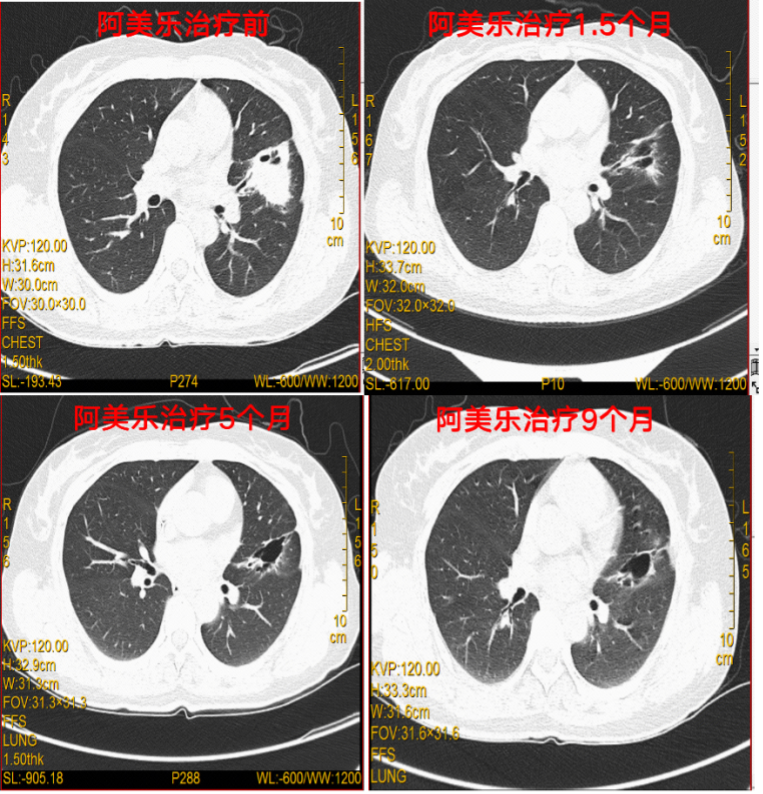

肺部病灶:一线阿美替尼联合化疗治疗6周疗效就达到PR,患者持续用药至今(2022.12),肺部疗效仍为PR。

图4:治疗期间胸部CT检查

脑转移病灶:一线阿美替尼联合化疗治疗颅内病灶,第二次疗效评估即治疗5个月(20220308)后疗效评价为PR,治疗12个月后(20221011)患者脑转移病灶疗效仍为PR。